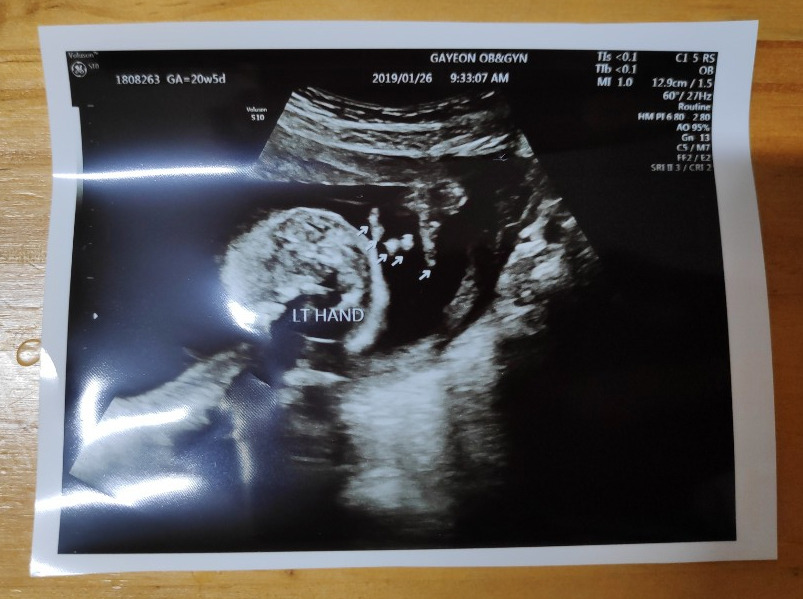

꼬톨이의 손과 발, 뇌, 장기 등이 정상적으로 자리 잡아가고 있는지를 보는 2차 정밀 초음파날!

초음파실에 들어가 하나하나 꼼꼼히 꼬톨이의 모습을 확인했다.

20분 정도 초음파를 본 것 같다. 손과 발 5개씩, 귀는 2개, 심장을 잘 뛰고 있는지.